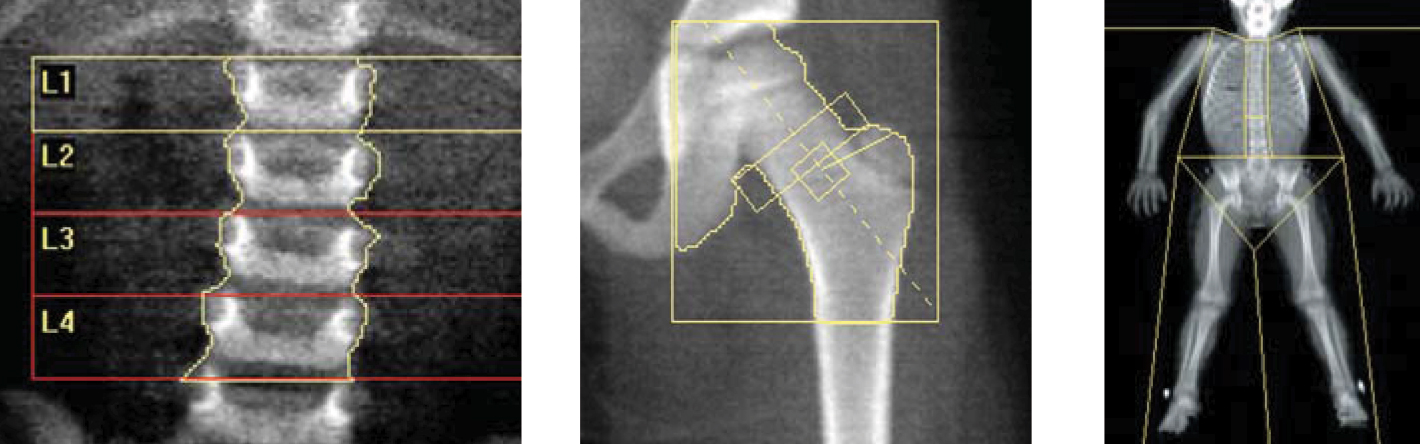

يعتبر قياس كثافة العظام عملية سهلة للغاية ، حيث يقوم النظام بالقياس في وقت قصير مثل 8 دقائق عندما يكون الشخص مستلقيًا على ظهره. في عيادتنا ، يتم إجراء قياس كثافة العظام باستخدام أحدث أجهزة العلامة التجارية جنرال إلكتريك / لونار.

يعد قياس كثافة العظام من أهم طرق التشخيص. يتم الفحص بجهاز خاص باستخدام جرعة منخفضة جدًا من الأشعة السينية. لا يتطلب الإجراء تحضيرًا أو دواء ، فهو يستغرق وقتًا قصيرًا. يتم إجراء قياس كثافة العظام في وحدتنا في غضون 10-20 دقيقة ، دون أي تحضير أولي ، دون أي حقن ، مع دعم الكمبيوتر.